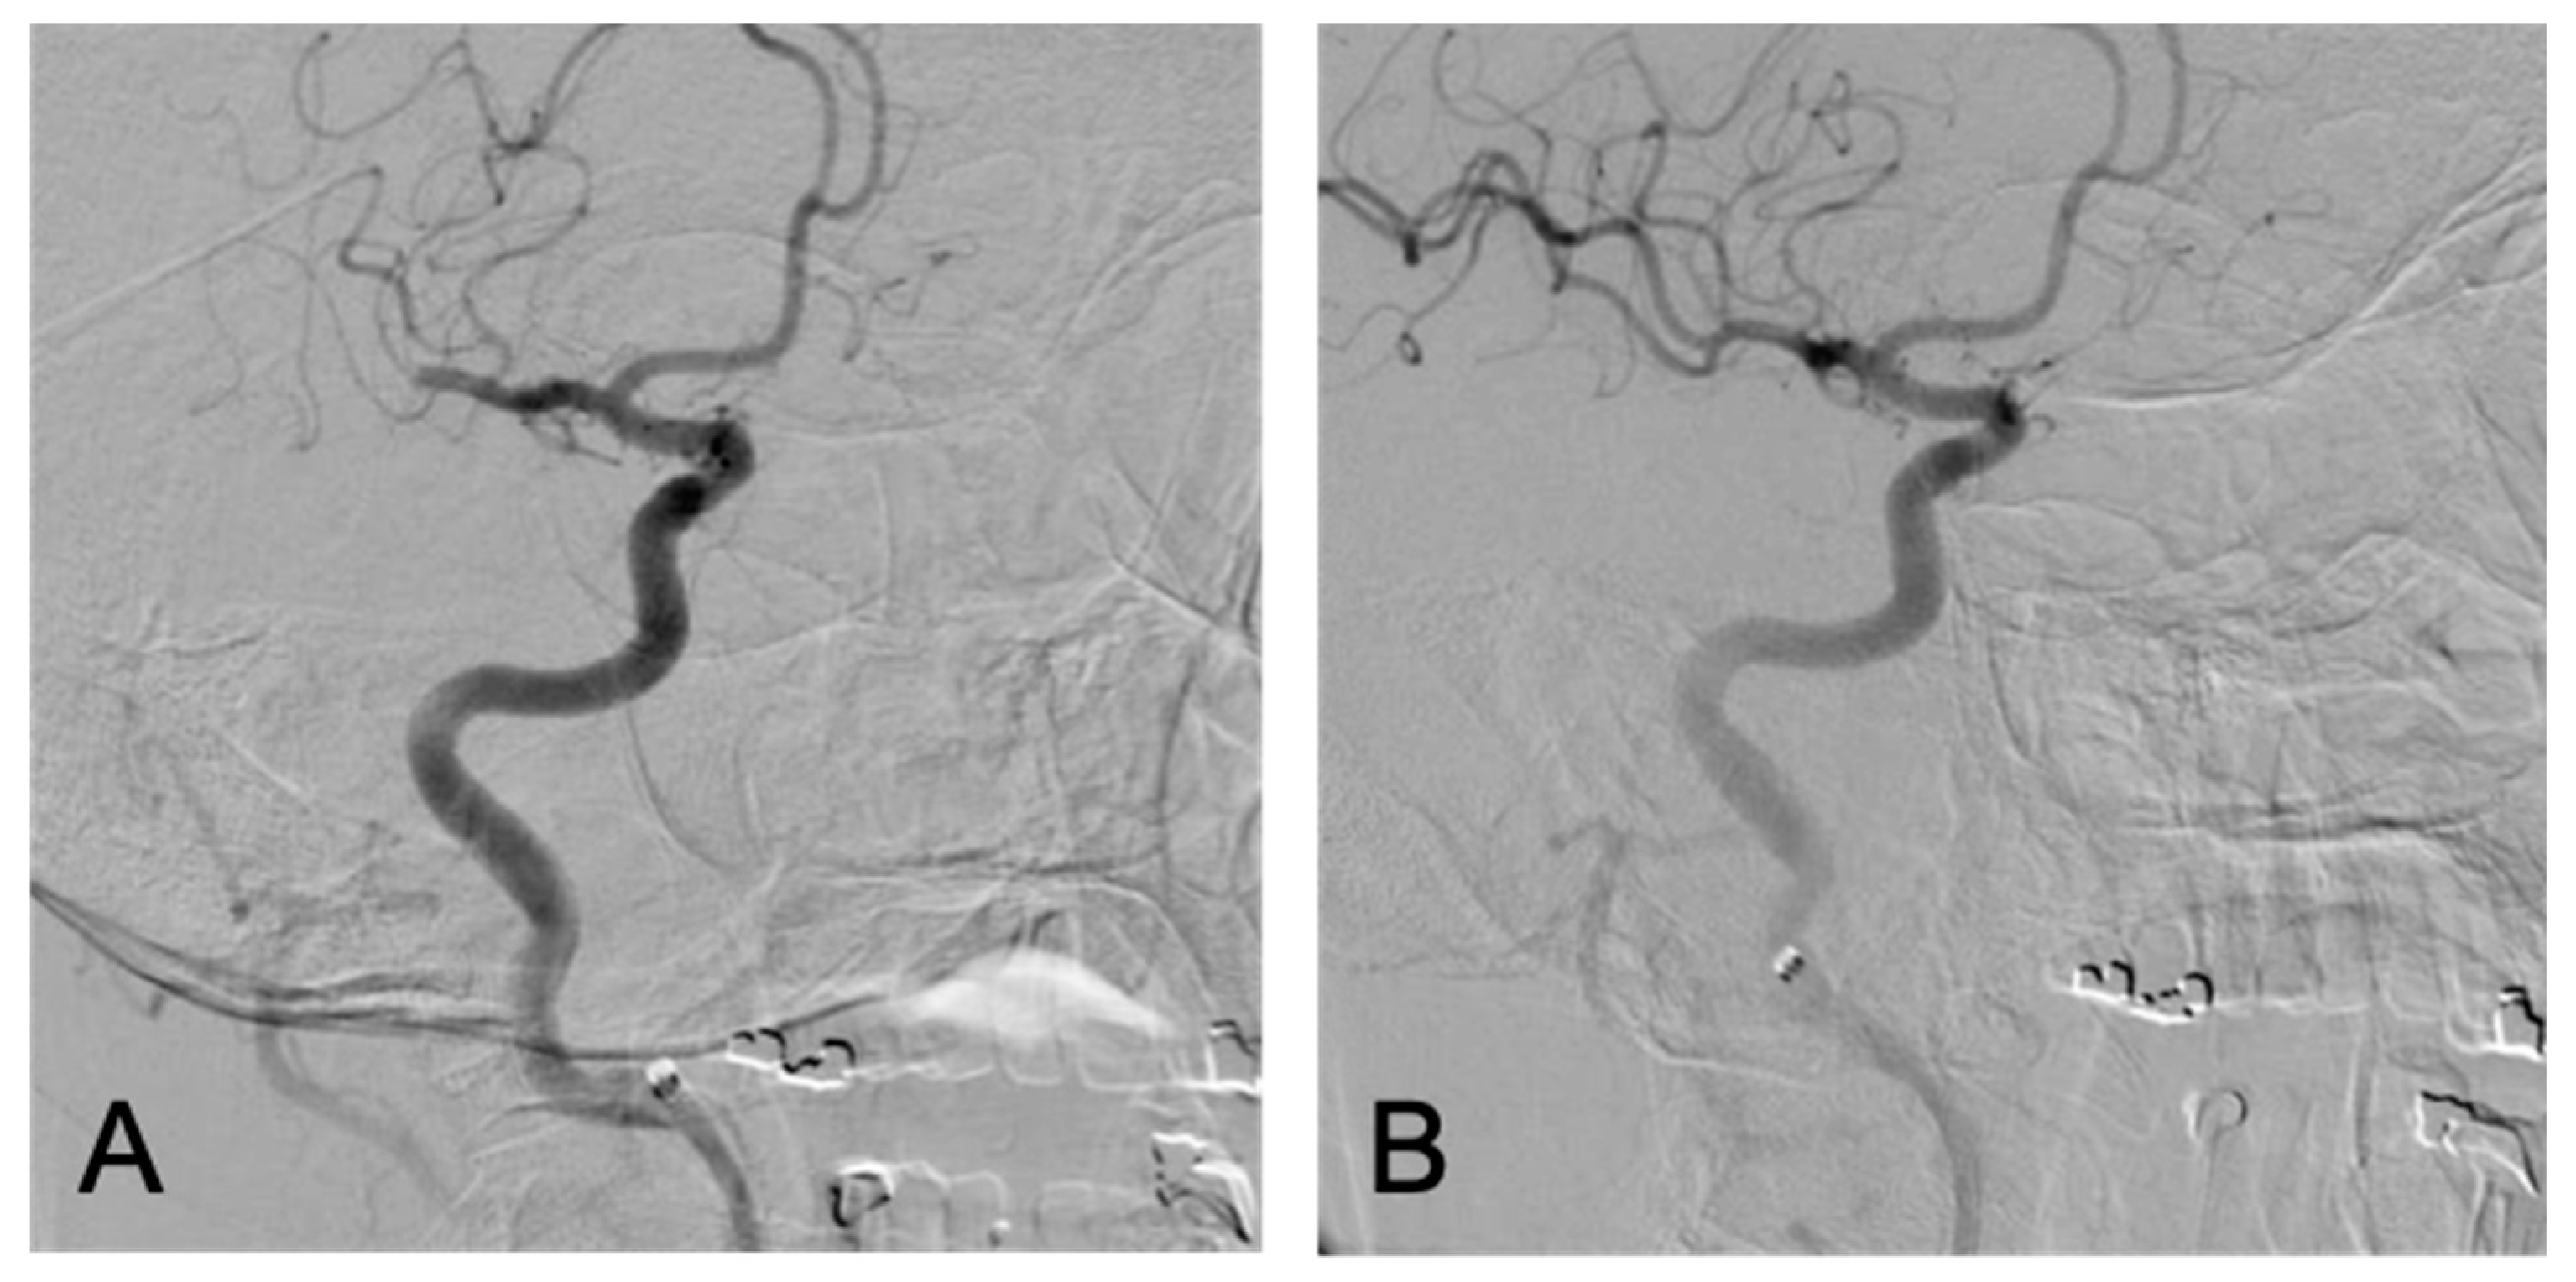

2. The Case